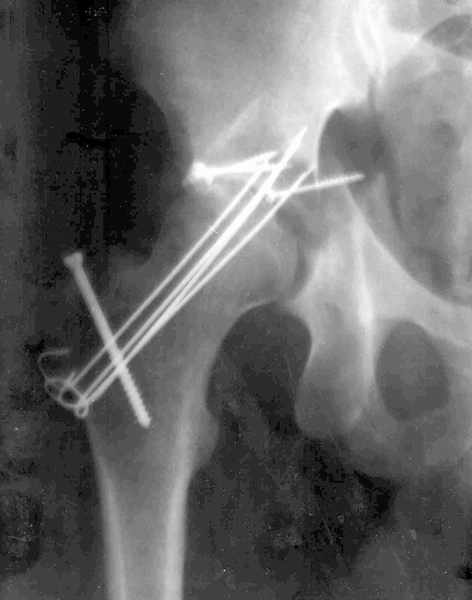

Xray CT Результат повторной операции

В нашей клинике 23.04.03 руководитель центра А.В. Рунков выполнил выездную показательную операцию. Не смотря на то, что с момента травмы прошло 2 месяца отломки вертлужной впадины были репонированы, восстановлена конгруэнтность суставных поверхностей тазобедренного сустава, фиксация реконструктивной пластиной. Операция была выполнена на высочайшем профессиональном уровне и её результат превзошёл мои ожидания. Ранний послеоперационный период протекает без осложнений, больной "воспрял духом", чувствует себя хорошо, занимается ЛФК, разработкой движений в коленном и тазобедренном суставах, сидит, ходит на костылях. На мой взгляд представленный случай является ярким примером целесообразности телеконференций, позволяющим достичь конкретного результата. Особую благодарность хочется выразить Александру Челнокову - организатору Форума. С Уважением Андрей Стасюк